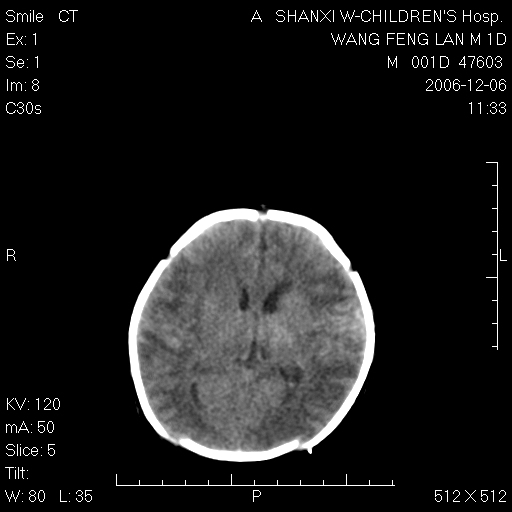

以下是引用husiling在2006-12-6 18:14:00的发言:[br]1\\hie[br]2\\蛛血.

以下是引用zjzjr在2006-12-6 19:29:00的发言:[br]支持新生儿缺血缺氧性脑病伴少量蛛网膜下腔出血.

以下是引用卜一在2006-12-6 21:38:00的发言:[br][br] 支持:新生儿缺血缺氧性脑病伴少量蛛网膜下腔出血 [br]